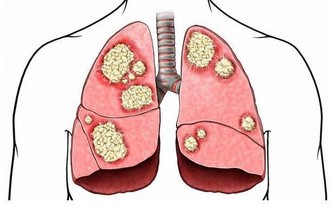

肺臟排毒

圖片來源

蘿蔔是肺臟的排毒食品:在中醫眼中,大腸和肺的關係最密切,肺排出毒素程度取決於大腸是否通暢,蘿蔔能幫助大腸排泄宿便,生吃或拌成冷盤都可以。

百合提高肺臟抗毒能力:肺臟向來不喜歡燥氣,在燥的情況下,容易導致積累毒素。蘑菇、百合有很好的養肺滋陰的功效,可以幫肺臟抗擊毒素,食用時加工時間不要過長,否則百合中的汁液會減少,防毒效果要大打折扣。

按壓肺臟排毒要穴:有利肺臟的穴位是合谷穴,位置在手背上,第1、2掌骨間,當第2掌骨橈側的中點處,可以用拇指和食指捏住這個部位,用力按壓。

排汗解毒:肺管理皮膚,所以痛痛快快地出一身汗,讓汗液帶走體內的毒素,會讓我們的肺清爽起來。除了運動以外,出汗的方法還可以是熱水浴,浴前水中加一些生薑和薄荷精油,使汗液分泌得更暢快,排出身體深處的毒素。

深呼吸:每次呼吸時,肺內都有殘餘的廢氣無法排出,這些廢氣相對於那些新鮮、富含氧氣的空氣來講,也是一種毒素。只需幾個深呼吸,就能減少體內廢氣的殘留。

肺臟最佳排毒時間:肺臟最強的時間是早7點~9點,此時最好能夠通過運動排毒。在肺最有力的時候進行慢跑等有氧運動,能強健肺排出毒素的功能。